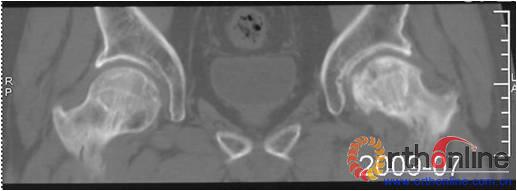

图 3 男,53岁,激素相关股骨头坏死,MRI(2003年)示右侧L1型坏死(皮质存留,骨髓坏死),左侧L3型坏死(皮质及骨髓均坏死),三年后(2006年)及6年后(2009年),CT扫描示右侧股骨头维持圆形,骨皮质完整,但中央坏死灶未修复;左侧股骨头塌陷

Fig 3 Male, 53 year-old, steroid-associated ONFH, MRI(2003) showed type L1 necrosis(cortical bone was preserved, necrosis in bone marrow) in right side; type L3 necrosis(both cortical bone marrow) in left side. CT scan showed the right femoral head keep round, and collapse occurred in left femoral head three (2006) and six year (2009) later.

3. 两种类型的ON有不同的结局,前者预后较好,而后者预后差。(图3)